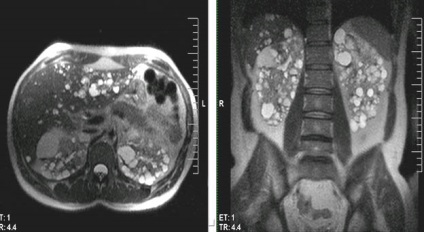

Ciszták a hasnyálmirigy